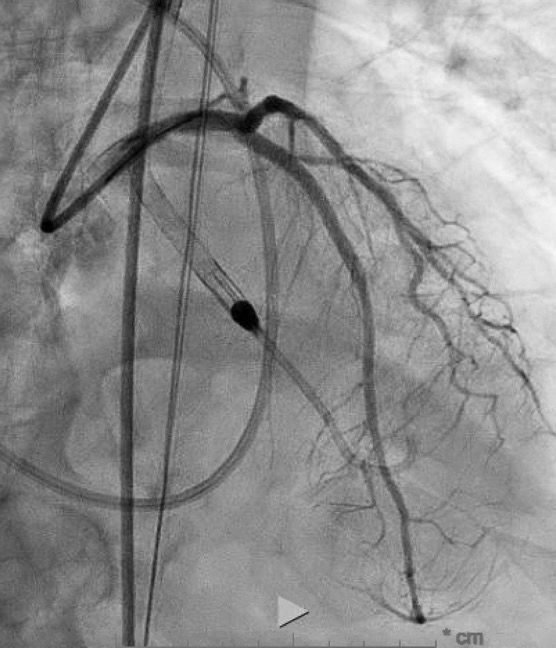

2/2 2/2 And…single-access Swan 🦒 monitored Impella-assisted IVUS πŸ‘οΈ guided LM-LAD-LCX DK Culotte Kiss πŸ’‹ POT 🍯 Kiss πŸ’‹ POT 🍯 PCI/DES: with device removal post-procedure (via single pre-close Perclose)…

1/2 Dec-Jan #LeftMain πŸ«€Chronicles continue. Advanced age. Cardiac arrest. NSTEMI. Moderate LV dysfunction. Severe LM bifurcation dz. Outside Hospital xfer post-recovery for PCI…